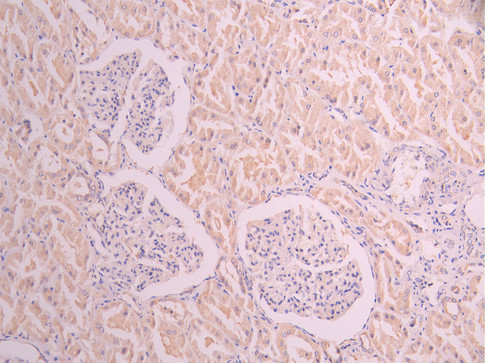

IHC image of CSB-RA010827MA1HU diluted at 1:50 and staining in paraffin-embedded human kidney tissue performed on a Leica BondTM system. After dewaxing and hydration, antigen retrieval was mediated by high pressure in a citrate buffer (pH 6.0). Section was blocked with 10% normal goat serum 30min at RT. Then primary antibody (1% BSA) was incubated at 4°C overnight. The primary is detected by a Anti-Human lgG, Fcy Fragment Specific labeled by HRP and visualized using 0.05% DAB.